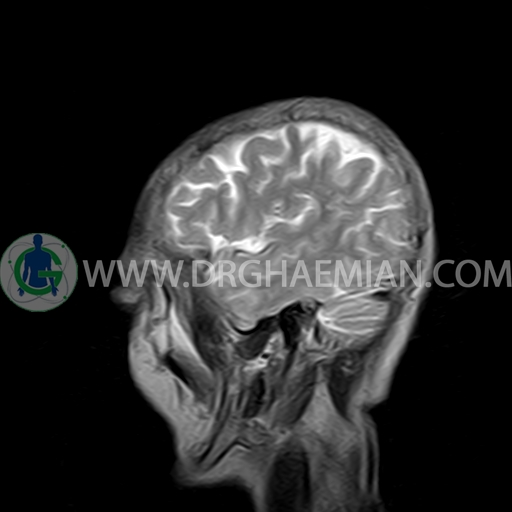

ام آر آی مغز با استفاده آهنربا های قوی و امواج رادیویی تصاویری از مغز و بافت های عصبی پیرامونی آن ایجاد می کند. در این کیس مننژیوم به همراه هیپراستوز استخوانی سمت چپ دیده می شود.

BRAIN MRI

(Without contrast)

Technique:Axial FLAIR, Axial, sagittal, FSE T2, coronal T1 .

a well – defined dural based mass lesion ( 27x55mm ) in left parietal region with signal change in adajacent bone suggestive for meningioma with bone hyperosteosis

mass effect & edema in left parietal lobe

are seen

COMMENT : MRI with contrast is recommended .